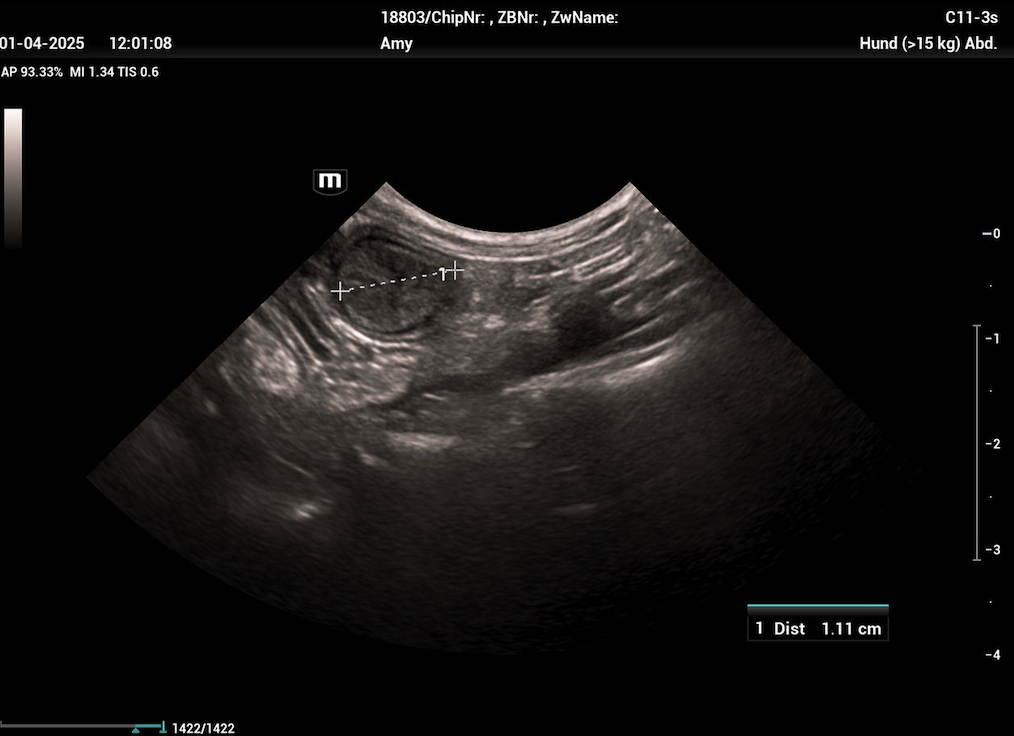

Die Uterusinvolution ist, verglichen mit anderen Spezies, beim Hund ein langsamer Prozess und kann je nach Studie 12 bis 15 Wochen dauernd. Die meisten Rückbildungsvorgänge finden in den ersten 4 bis 6 Wochen post partum statt und in dieser Zeit zeigt die Hündin auch einen geruchlosen, anfangs grünlichen (aufgrund des Uteroverdins der Plazenta) dann eher dunkelroten bis braunen vaginalen Ausfluss, der im Laufe dieser Wochen kontinuierlich abnimmt. Mit diesen Lochien werden Teile der Gebärmutterschleimhaut abgebaut, die aufgrund des epitheliochorialen Aufbaus der Plazenta beim Hund erneuert werden müssen.

Sollen bei der Geburt nicht alle Plazenten vollständig gesehen worden sein, empfiehlt sich immer eine Kontrolle mittels Vaginoskopie und Ultraschall. Sind Ganze oder auch nur Teile davon im Uterus verblieben und nicht vaginal zu entfernen, kann auch hier Oxytocin gegeben werden um die Uteruskontraktionen und somit die Ablösung der Plazenta zu fördern. (1-(3) I.E. 2-3 mal täglich (Arnold 2000a)). Innerhalb der ersten Tage nach der Geburt sinkt jedoch die Oxytocinrezeptorexpression im Myometrium bereits rapide ab, sodass eine längere Gabe oft nicht den gewünschten Erfolg bringt. Gleichzeitig sollte man eine gute Breitbandantibiose (bei säugenden Hündinnen meist Amoxicillin/Clavulansäure) und im Bedarfsfall auch ein Nicht-steroidales Antiphlogistikum verabreichen. Sollte sich die Plazenta nicht lösen, muss sie vom Körper resorbiert und die Hündin somit weiterhin engmaschig überwacht werden. Im schlimmsten Fall kann auch hier eine OP nötig werden.